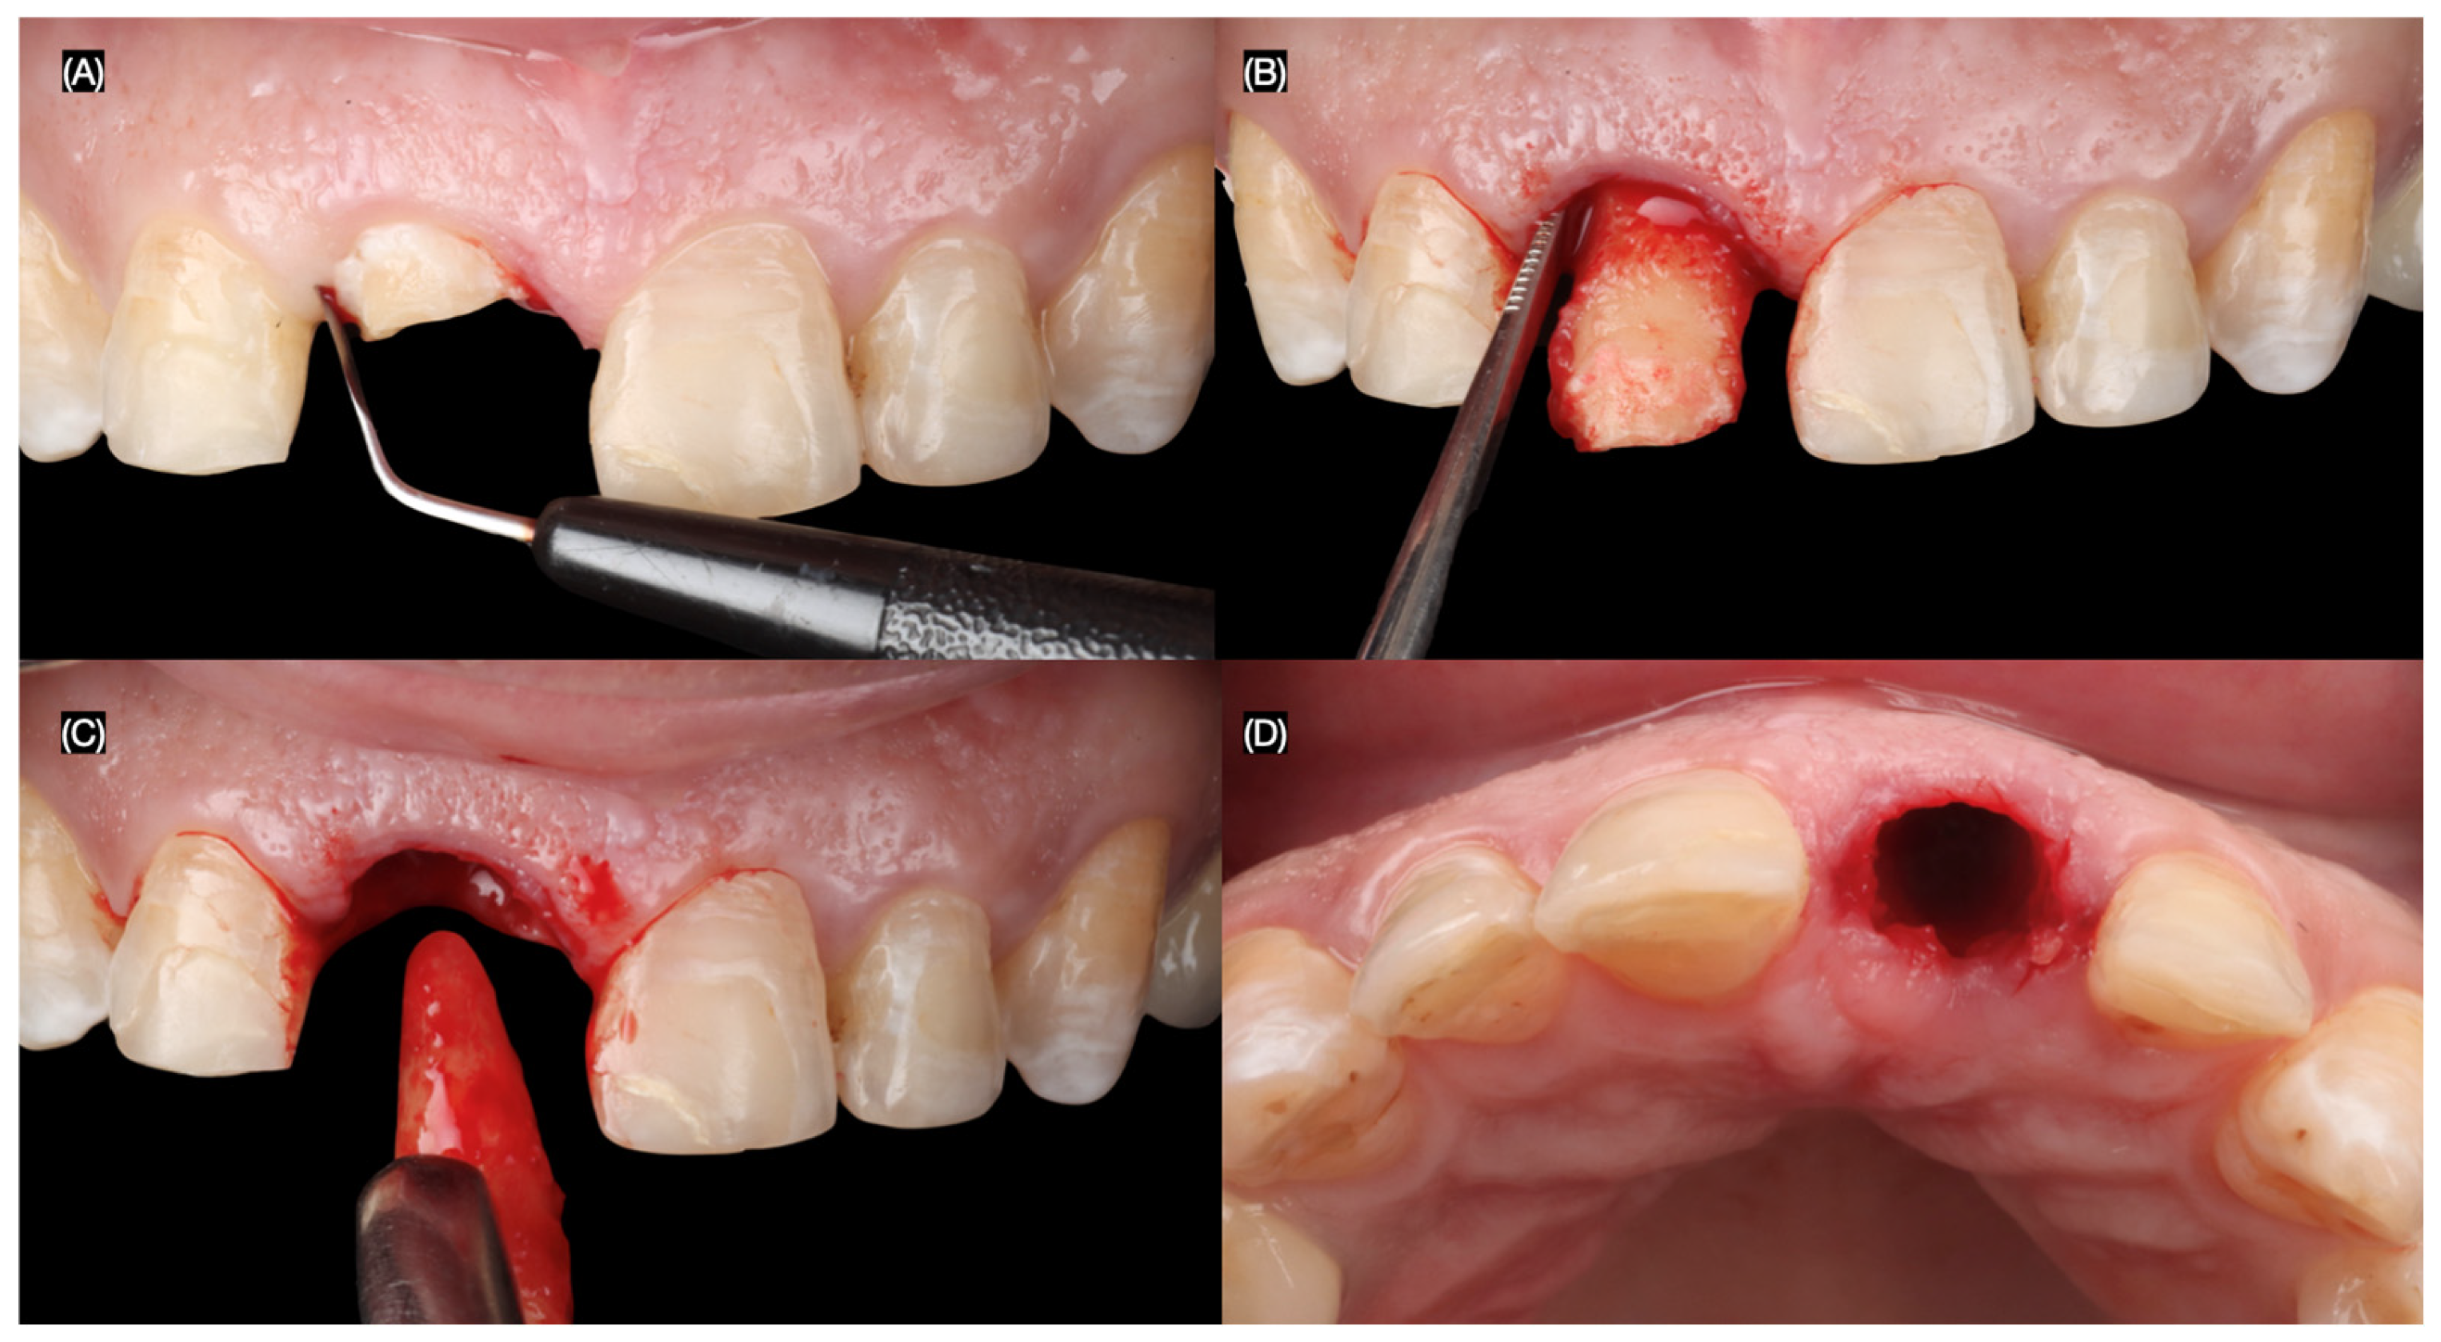

The maxillary right central incisor was extracted atraumatically, preserving the surrounding bone and soft tissues. An immediate implant (MISC C1, 3.30 mm × 13 mm, MIS Implant, Misgav, Israel) was placed using a surgical guide, ensuring precise positioning and primary stability (Figure 4 and Figure 5).

Figure 4.

Flapless atraumatic tooth extraction. (A) Desmotomes insertion, (B) luxation of root, (C) extraction, and (D) incisal view after extraction.